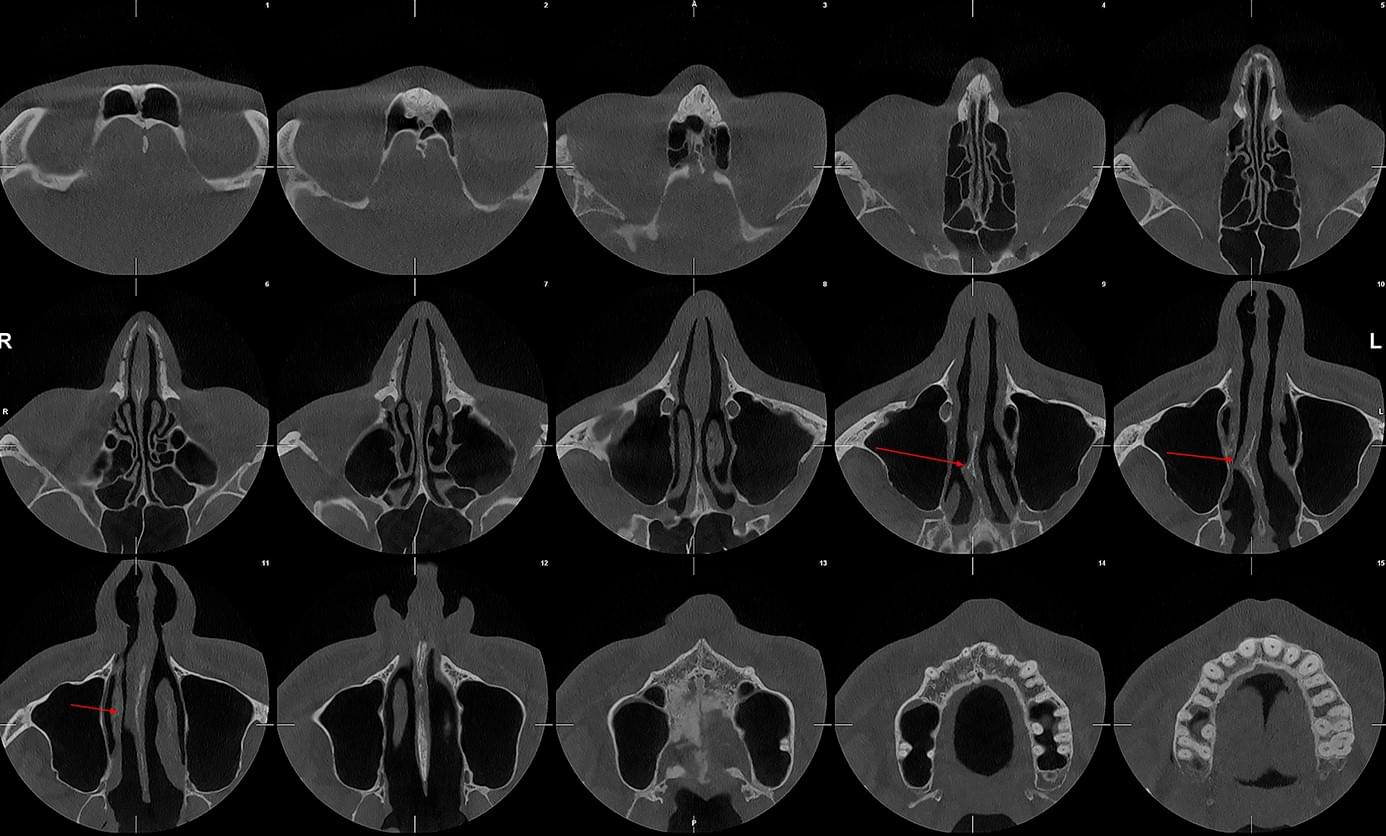

КПКТ (конусно-променева комп’ютерна томографія) — це 3D-знімок високої роздільної здатності. На відміну від звичайного рентгену, КТ показує:

У MyRayLab використовують сучасний апарат Planmeca 3D — доза опромінення всього 12 мкЗв (в 10–20 разів нижче, ніж у звичайних КТ), сканування 10 секунд, HD-якість.

Діагностика гайморових пазух за допомогою КТ

У сучасній медицині КТ придаткових пазух носа (або КТ синусів) — це «золотий стандарт»

діагностики для ЛОР-лікарів та щелепно-лицевих хірургів. Звичайний рентген часто не

показує повну картину, а МРТ не завжди доступний і дорожчий. Комп’ютерна томографія дає

детальну 3D-модель усіх пазух (гайморових, лобних, клиновидних та решітчастого

лабіринту) за 10 секунд і з мінімальною дозою опромінення.